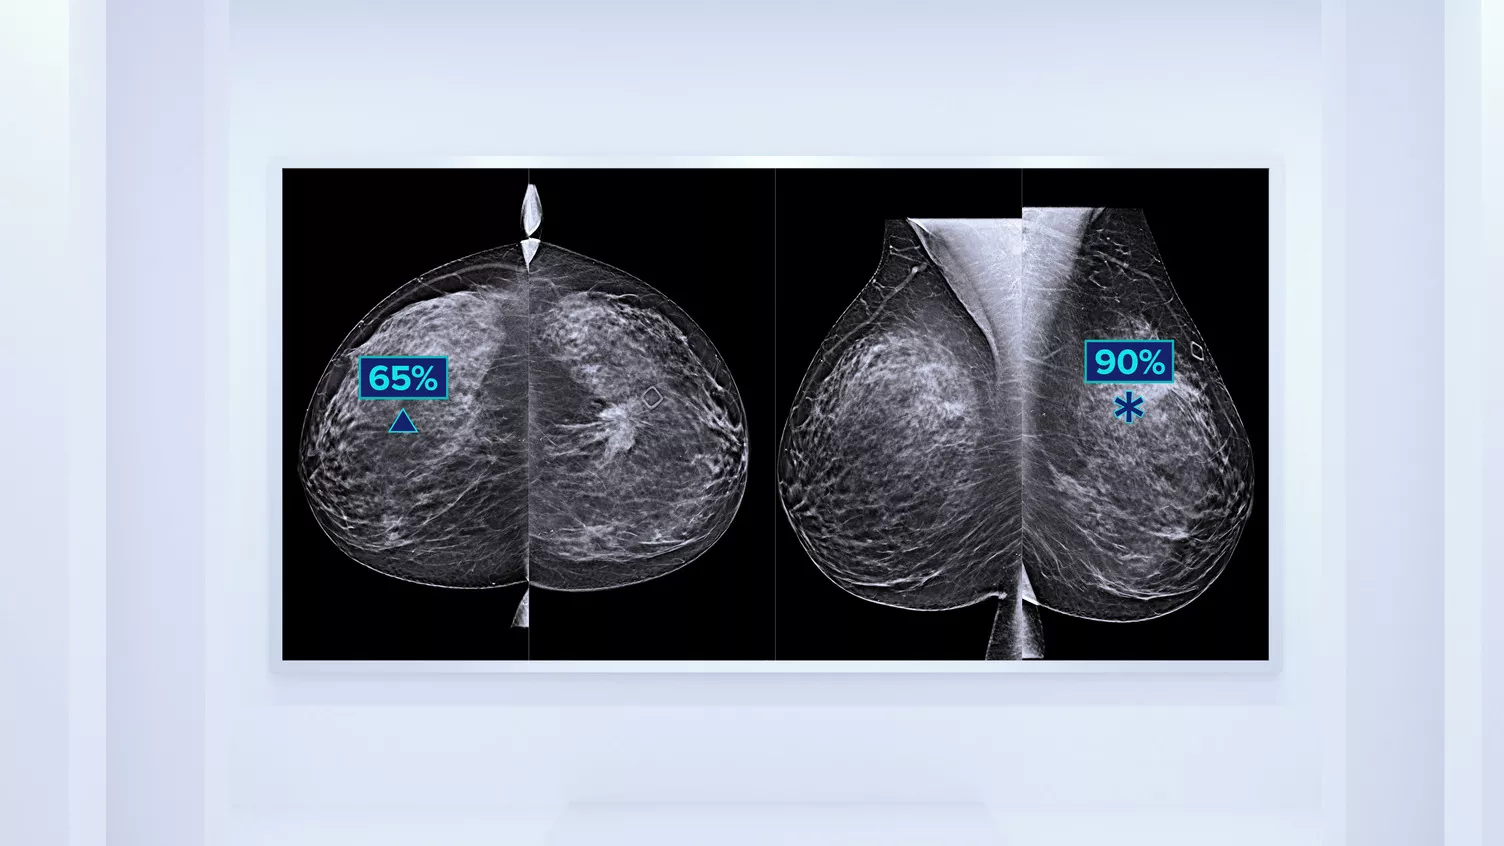

Better Risk Prediction

In addition to volume, pattern and texture of fibroglandular tissue may play just as an important role in mammographic cancer risk prediction.3-5 By analysing and categorising breast texture and pattern, our technology can deliver the accurate information you need to achieve more consistent and reliable scoring and confidently design patient-specific screening.

Risk Categories8